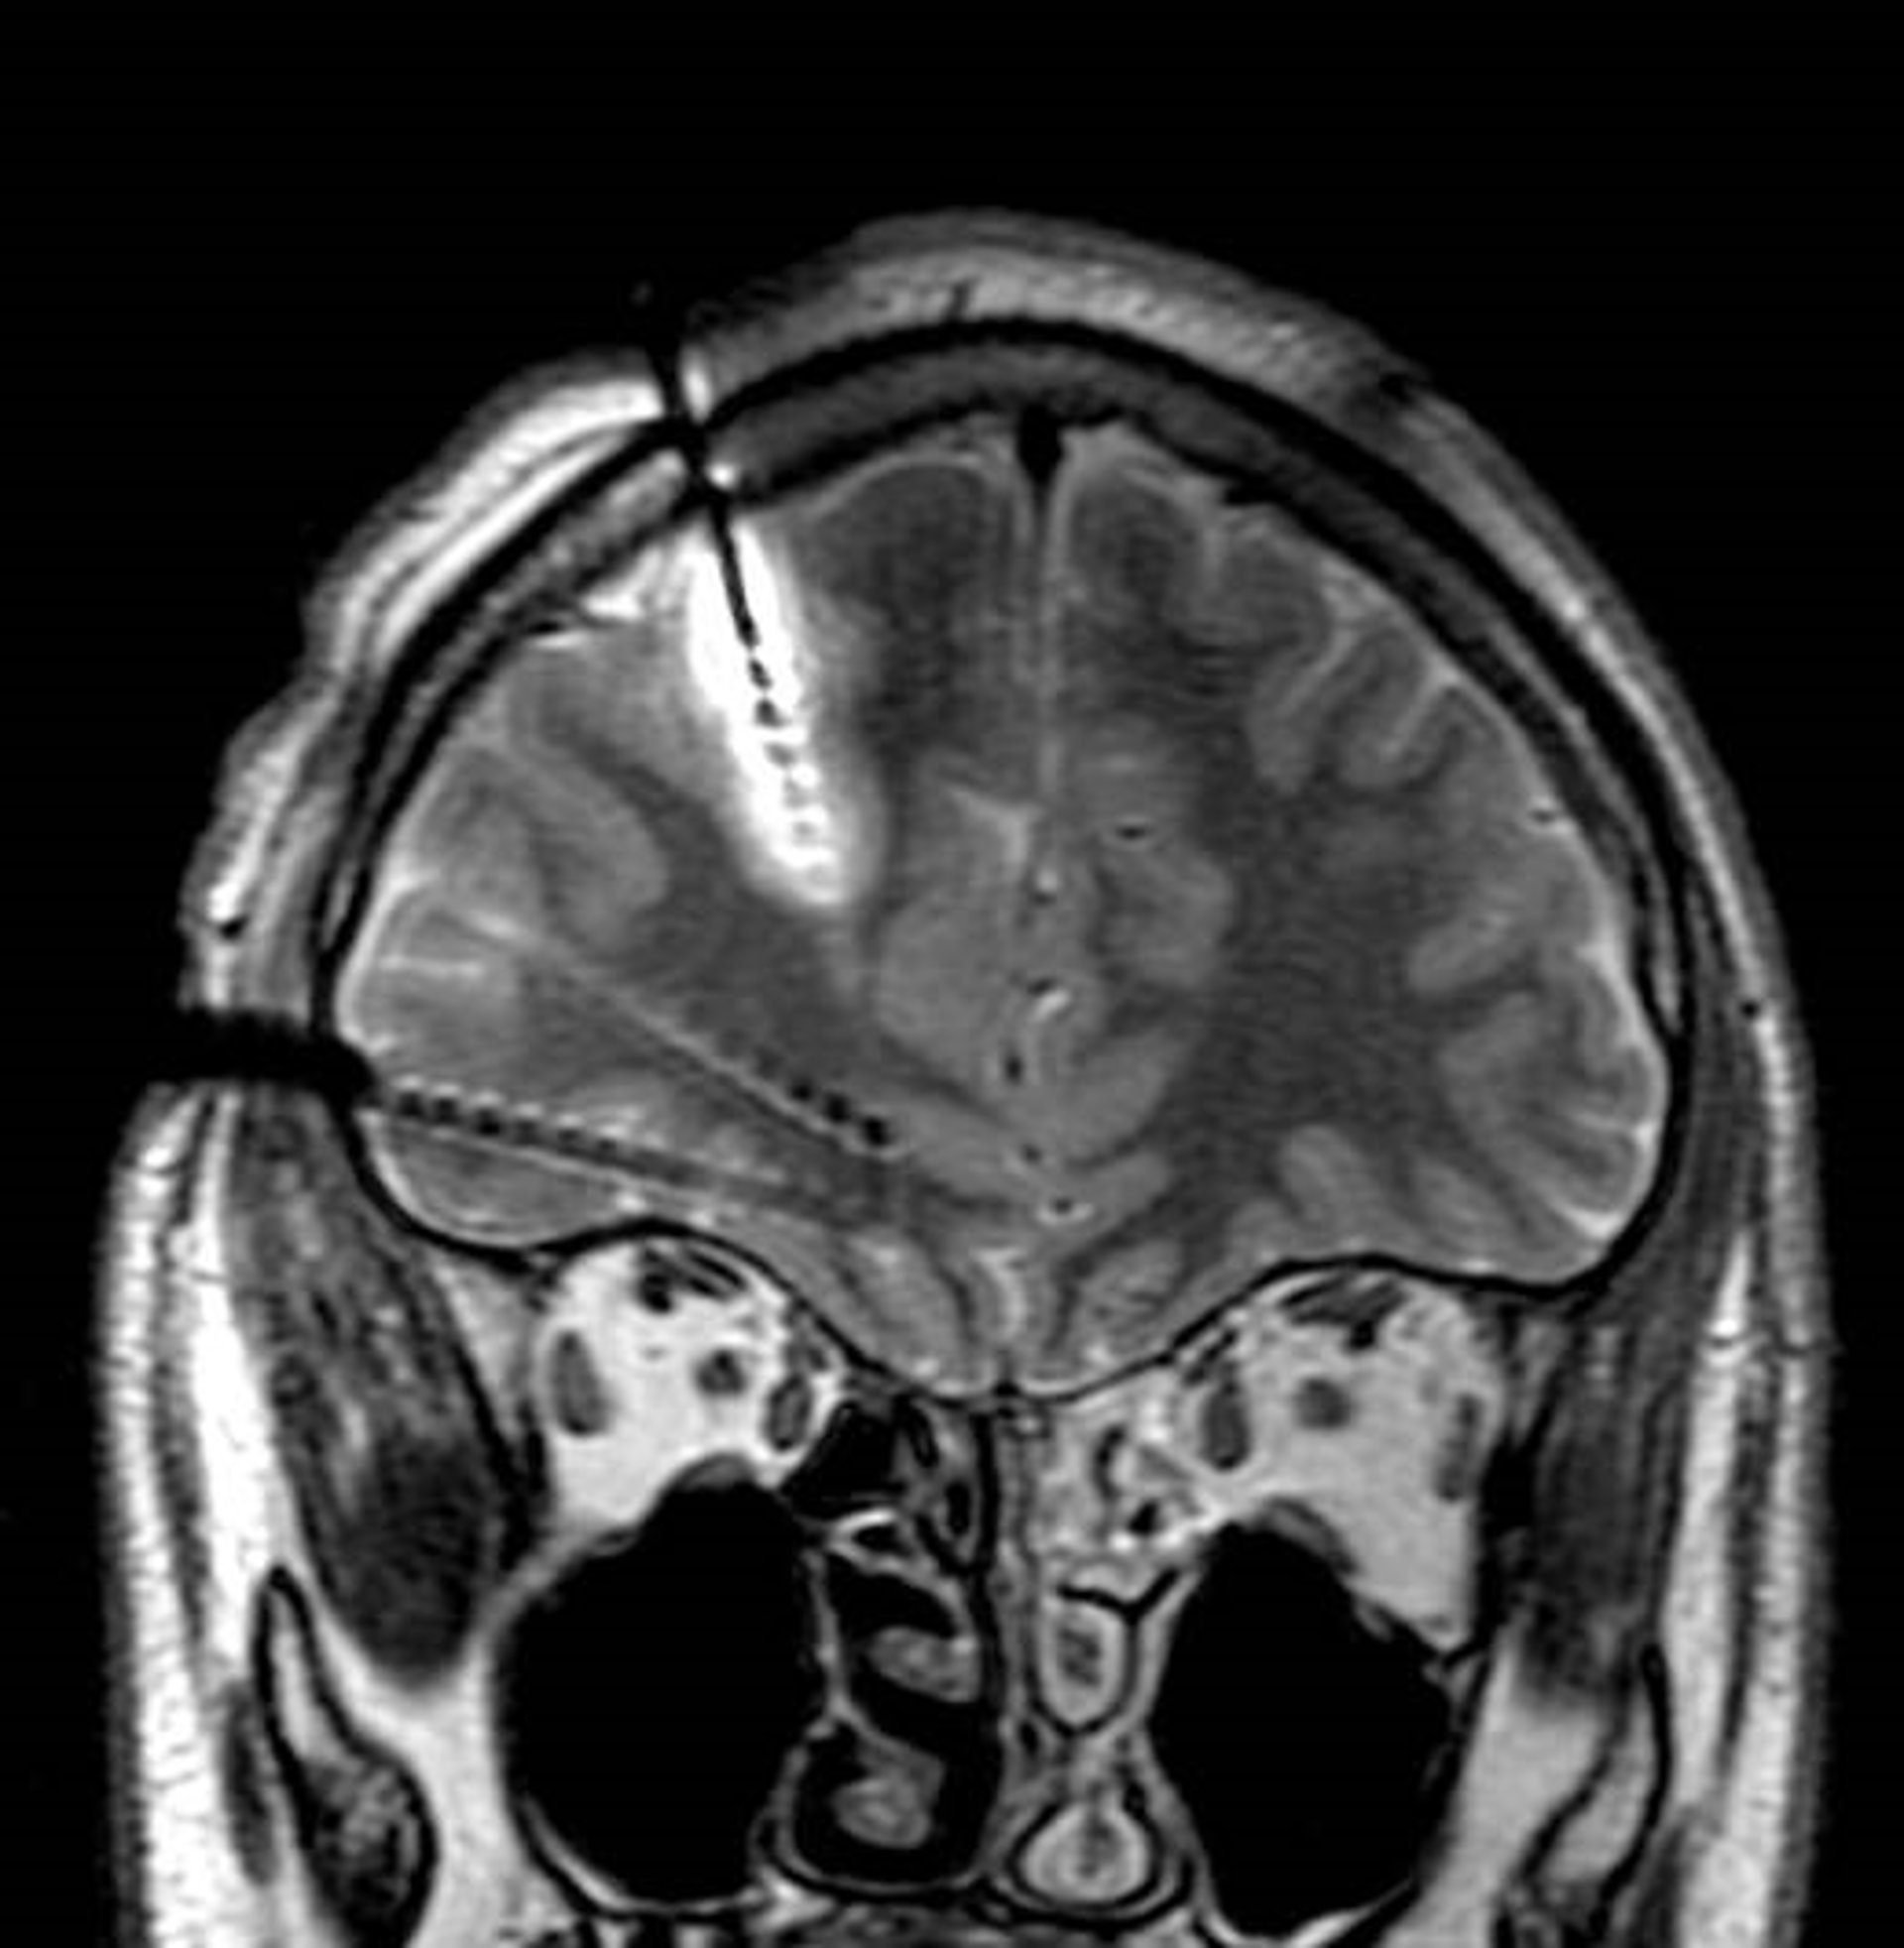

En la imagen se aprecia cómo ha sido implantado uno de los electrodos mostrando una lesión en esa localización alrededor del electrodo realizándose termocoagulación.

Esta técnica, basada en electrodos profundos y termocoagulación, se ha validado a través del primer estudio en pacientes españoles sobre este procedimiento, que se ha publicado en la revista 'Neurología', editada por la Sociedad Española de Neurología (SEN). Los buenos resultados que se extraen del estudio son similares a los de otros proyectos llevados a cabo a nivel internacional, en países como Francia, Italia y Estados Unidos.

El trabajo, realizado en 71 niños y adultos, indica que esta nueva técnica permite localizar el foco epiléptico en muchos pacientes en los que antes no era posible. Una vez localizado el foco puede tratarse mediante termocoagulación, que utiliza los mismos electrodos ya implantados y que es menos invasivo que otras técnicas, o incluso, proceder a la cirugía. En el 90 por ciento de los casos, fue posible identificar el foco epiléptico y tratarlo mediante termocoagulación o cirugía. Además, en el 77 por ciento el resultado de la cirugía ha sido positivo.